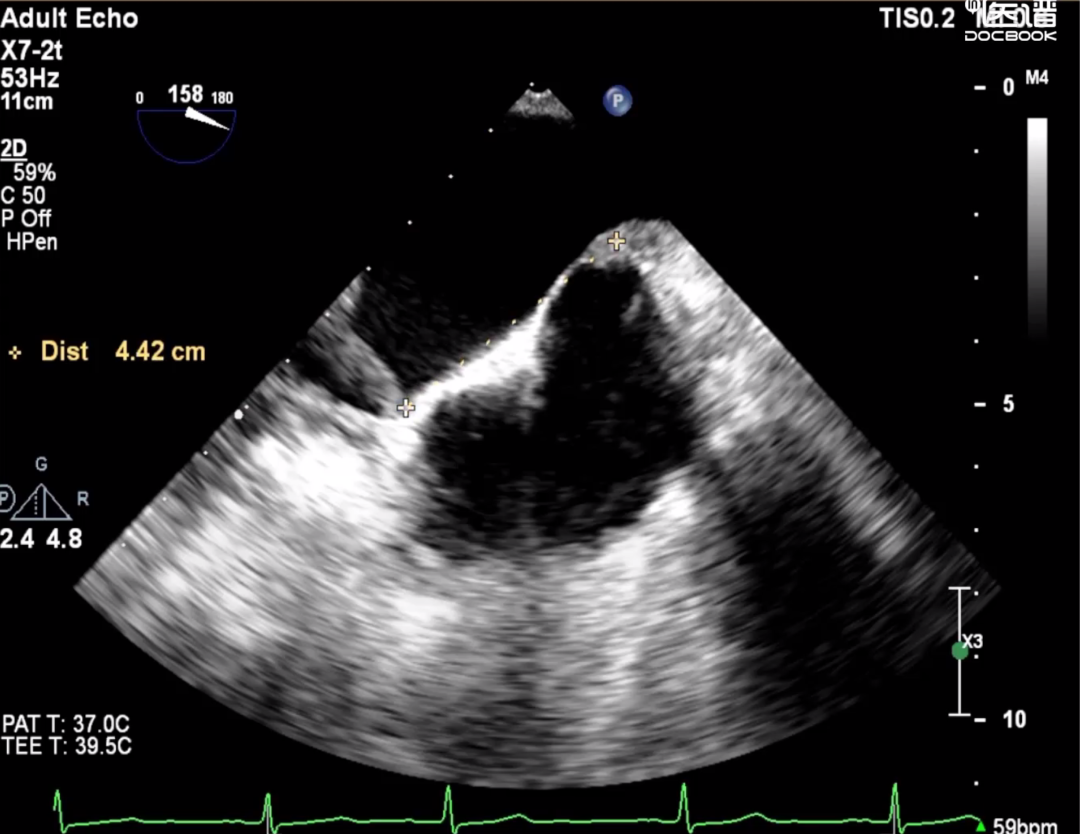

图2:P2P1间有一连续性中断,为瓣叶裂

图3:房间隔高度

图4: 成功夹合二尖瓣P1P2区,超声显示P2区外侧脱垂